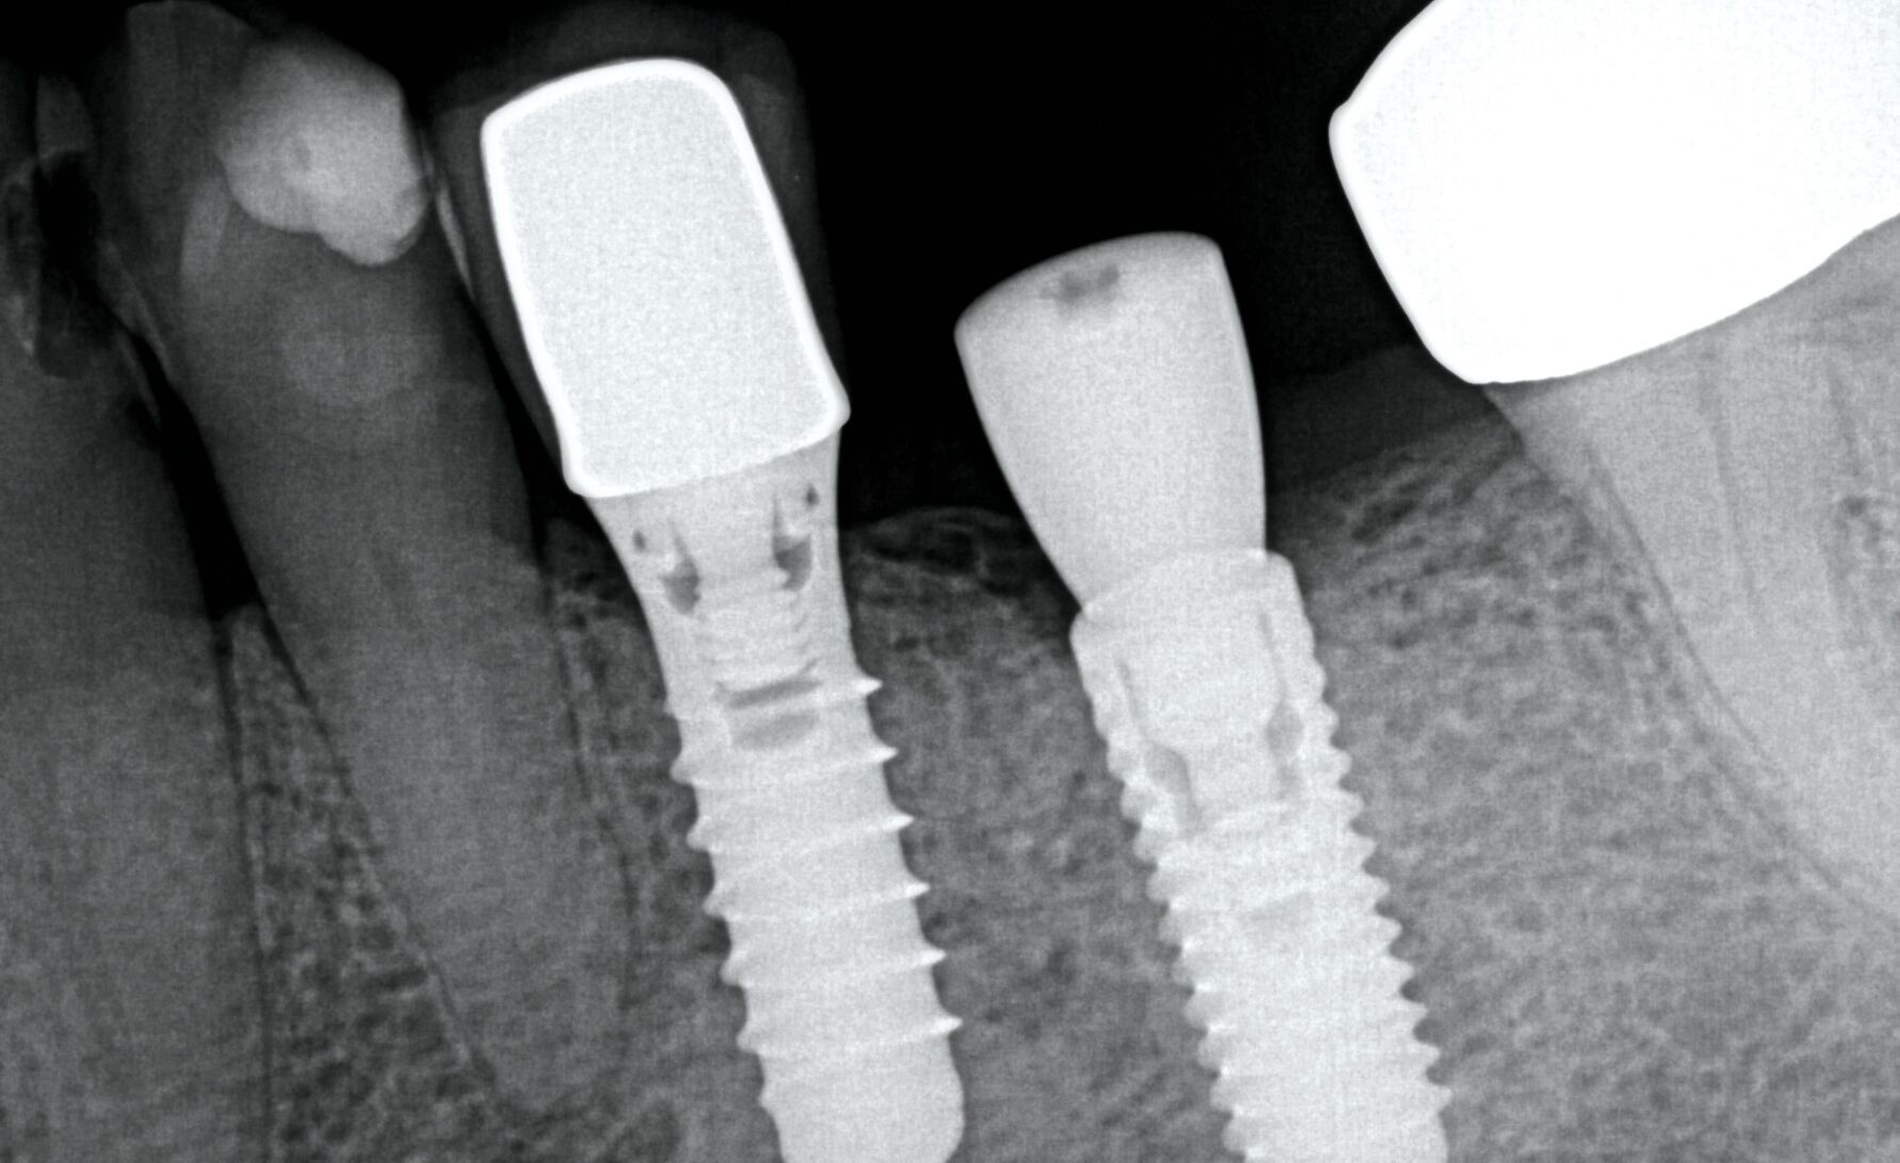

Das Abutment war oberhalb der Implantat-Schulter gebrochen. Obwohl die Befestigungsschraube mit dem Standardwerkzeug einfach zu lösen war, ließ sich das Abutment-Fragment nicht entfernen. Also wurde das Restfragment mit einem Spezialwerkzeug (Konus-Adapter mit Linksgewinde für die passende Ratsche) entfernt. Wichtig ist dabei, darauf zu achten, dass das Innengewinde nicht verformt wird. Um ein zu festes Eindrehen zu vermeiden, kann dies mittels eines Zahnfilms überprüft werden (Abbildung 1). Nach der Lageüberprüfung wird der Konus-Adapter mit circa 30 – 35 Ncm festgezogen und das Fragment durch Rütteln entfernt. Sollte dies nicht zum Erfolg führen, kann man mittels Ultraschall auf den Adapter einwirken (Abbildung 2).

In diesem Fall war das Abutment in regio 36 etwa sieben Jahre nach der prothetischen Versorgung frakturiert. Beim Versuch, die Krone zu entfernen, kam es zusätzlich zur Separation der Befestigungsschraube. Beide Fragmente konnten mithilfe eines systemspezifischen Spezialwerkzeugsatzes (zum Beispiel Reparaturset von Ankylos, Dentsply Sirona) entfernt werden.

Das herstellerseitig empfohlene Vorgehen sieht vor, das Abutmentfragment zentral mit einem runden Bohrer oder Diamanten (Ø 1,2–1,4 mm) anzukörnen. Anschließend erfolgt die Bohrung mit einem speziellen Kernlochbohrer (Ø 1,8 mm, Tiefe circa 3 mm) bei 1800 U/min und unter Kühlung. Ein passender Extraktionsstift wird eingeschraubt und das Schraubenfragment mithilfe eines Ausdrehers entfernt. Für verbliebene Gewindehülsen stehen spezielle Ausdrehinstrumente zur Verfügung; in schwierigeren Fällen kann zusätzlich ein Spiralbohrer (1,4 mm) zum Einsatz kommen. Der finale Schritt besteht in der Nachbearbeitung des Innengewindes mit einem Gewindeschneider (M1,8). Zur Minimierung des Friktionswiderstands kann die Verwendung eines Gleitmittels (zum Beispiel Vaseline) hilfreich sein. Ein verkantungsfreies Arbeiten ist essenziell, um Instrumentenbruch und Implantatverlust zu vermeiden. Die radiologische Darstellung des Bruchs sowie die Situation nach Entfernung der Komponenten sind in den Abbildungen 3 und 4 dokumentiert.